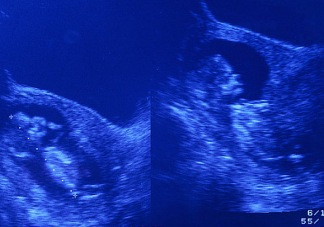

什么是胎心胎芽 懷孕多長(zhǎng)時(shí)間能看到胎心胎芽

受精卵慢慢發(fā)育成胚胎逐漸形成胎兒,孕期檢查一般會(huì)檢查胎心胎胎芽,孕早期胎心胎芽是否健康正常關(guān)系到胎兒的健